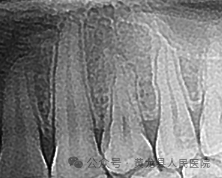

比如当牙齿有深部龋坏时,仅凭口内检查无法得知龋坏的深度、距离牙神经的距离以及有没有并发牙根周围发炎等重要信息,以此确定是否需要进行根管治疗。当拔除下颌智齿时,仅凭口内检查无法发现它离神经管的位置。

因此,如果牙齿出了问题,牙科医生就需要有“透视”功能的X线片来检查。通过x线片不仅能了解牙齿本身的病变情况,还可以了解牙根下有没有囊肿、周围骨头有没有吸收以及牙槽骨内是否有埋伏牙、多生牙等。依据X线片综合分析,可以提高牙科医生诊断与治疗的准确性和成功率。